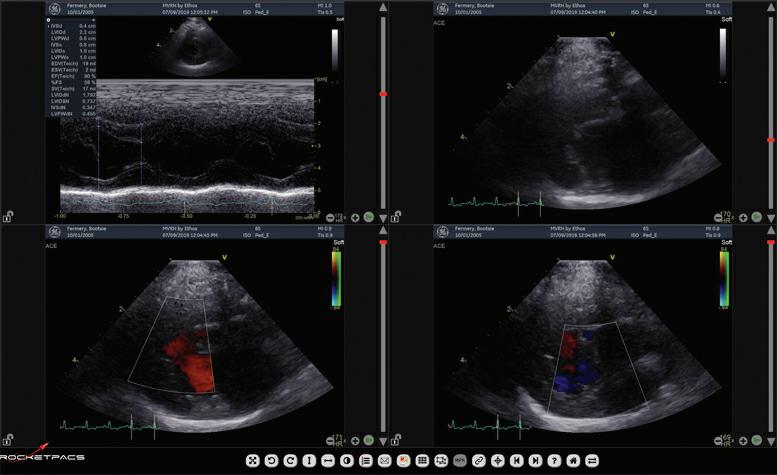

Interventional Radiology at Animal Referral Hospital (ARH) Homebush

ARH Homebush’s Internal Medicine Specialist, Dr Tim Hugo BVSc (Hons 1) FANZCVS (Small Animal Medicine) recently undertook specialised training in cardiac interventional radiology procedures in the USA led by renowned professor of cardiology at Colorado State University Dr. Brian Scansen. Focused on treating common congenital heart diseases such as patent ductus arteriosus and pulmonic stenosis, the training emphasised catheter-based treatments. Interventional Radiology offers new possibilities for conditions previously treated with open surgery, resulting in reduced patient morbidity and shorter hospital stays. ARH Homebush provides various interventional radiology treatments, including stenting and coiling for intrahepatic portosystemic shunts.